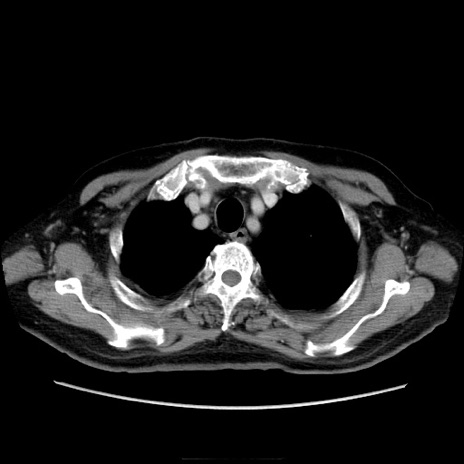

症例21(横断像)

【症例】70歳代男性

【主訴】腹痛

【現病歴】肝硬変・肝細胞癌にてかかりつけの方。約9時間前に食後より腹痛出現。症状が徐々に増悪し、嘔吐出現したため来院。

【既往歴】肝硬変、肝細胞癌(RFA、TACE後)

【身体所見】意識清明、表情苦悶様、BT 36℃、BP 129/78mmHg、P 88bpm、SpO2 97%(RA)、右上腹部から心窩部にかけて圧痛あり、反跳痛なし、筋性防御あり。

【データ】WBC 5800、CRP 0.16